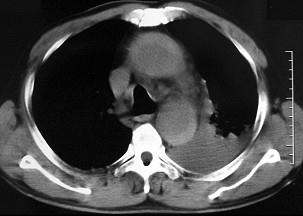

问题 男,58岁,有高血压病史,突发胸背剧痛,CT扫描如图,其最可能的诊断为 ( )

选项 A.主动脉瘤 B.主动脉假性动脉瘤 C.主动脉窦瘤破裂 D.高安氏病 E.主动脉夹层动脉瘤

答案 E